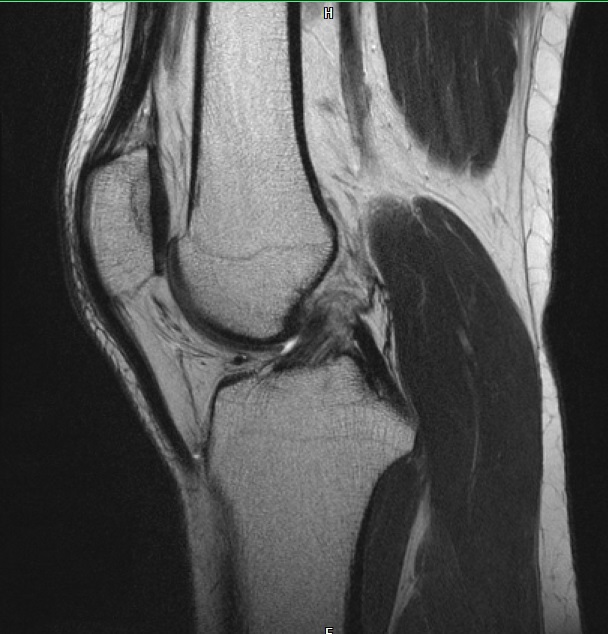

Ich war gerade im MRT wegen Problemen mit meinem rechten Knie. Hab jetzt kurz mal einen auf Dr. Google gemacht und Bilder der häufigsten Verletzungen verglichen mit meinen Bildern. Da bin ich beim vorderen Kreuzbandriss etwas aufmerkasm geworden. Das sind meine Bilder

auf dem letzten Bild sieht man mein hinteres Kreuzband ja wunderbar, es ist ja dieser dunkle "Haken", der Oberschenkel und Schienbein miteinander verbindet.

Nun aber auf dem 3. Bild sollte man doch dasselbe fürs vordere sehen? Aber ich sehe da nur die Ansätze am Schienbein?